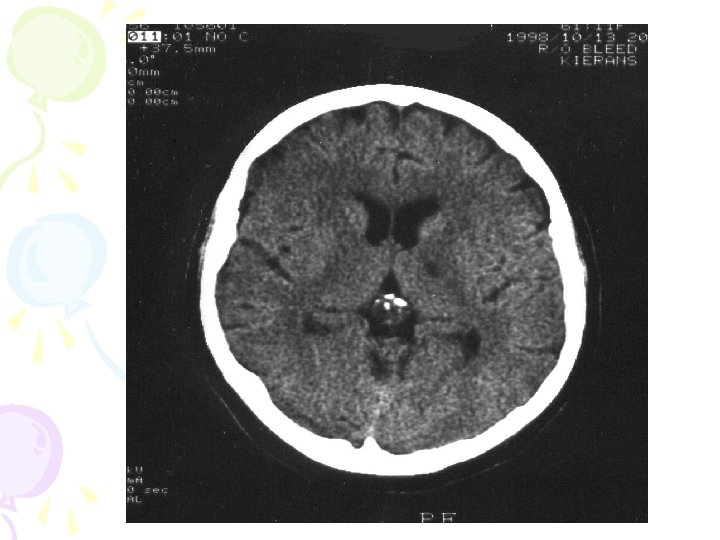

How do we know about the brain? • EEG- electrical activity • CAT- 3 D images • MRI- radio waves/Hydrogen atom energy • PET- chemical activity after injection of radioactive substance

Computed Tomography (CT or CAT Scan) • X-ray photographs 3 D representation of the brain • More widely available, faster, easier, less expensive than MRI